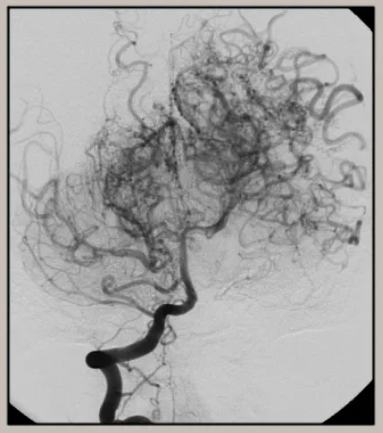

모야모야병은 뇌혈관이 점차 좁아지거나 막히며 뇌가 이를 보완하기 위해 가는 혈관을 생성하는 희귀 질환이다.

일본어로 ‘희미하게 보이는 연기’를 뜻하는 모야모야(もやもや)에서 유래된 이 병은 주로 소아에서 발견되지만 성인에게도 발병할 수 있다.

대표적인 치료는 혈관 우회술(뇌 혈류 재건술)로 뇌에 새로운 혈류 통로를 만들어 증상을 완화하고 뇌졸중 위험을 줄이는 방식이다. 조기 발견과 치료가 중요한 만큼, 특히 가족력이 있는 경우 주기적인 뇌혈관 검진을 받는 것이 중요하다.